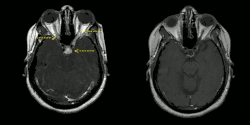

Left image: MRI findings (T1-weighted images) in a patient with neurosacoidosis showing thickening of infundibulum and both optic nerves (white signal marked with yellow arrows; width 6 mm).

Right image: MRI brain with contrast showing near resolution of enhancement after treatment.

The diagnosis of neurosarcoidosis often is difficult. Definitive diagnosis can only be made by biopsy (surgically removing a tissue sample). Because of the risks associated with brain biopsies, they are avoided as much as possible. Other investigations that may be performed in any of the symptoms mentioned above are computed tomography (CT) or magnetic resonance imaging (MRI) of the brain, lumbar puncture, electroencephalography (EEG) and evoked potential (EP) studies. If the diagnosis of sarcoidosis is suspected, typical X-ray or CT appearances of the chest may make the diagnosis more likely; elevations in angiotensin-converting enzyme and calcium in the blood, too, make sarcoidosis more likely. In the past, the Kveim test was used to diagnose sarcoidosis. This now obsolete test had a high (85 percent) sensitivity, but required spleen tissue of a known sarcoidosis patient, some of which was injected into the skin of a suspected case.[1]

MRI with gadolinium enhancement is the most useful neuroimaging test. This may show enhancement of the pia mater or white matter lesions that may resemble the lesions seen in multiple sclerosis.[1]